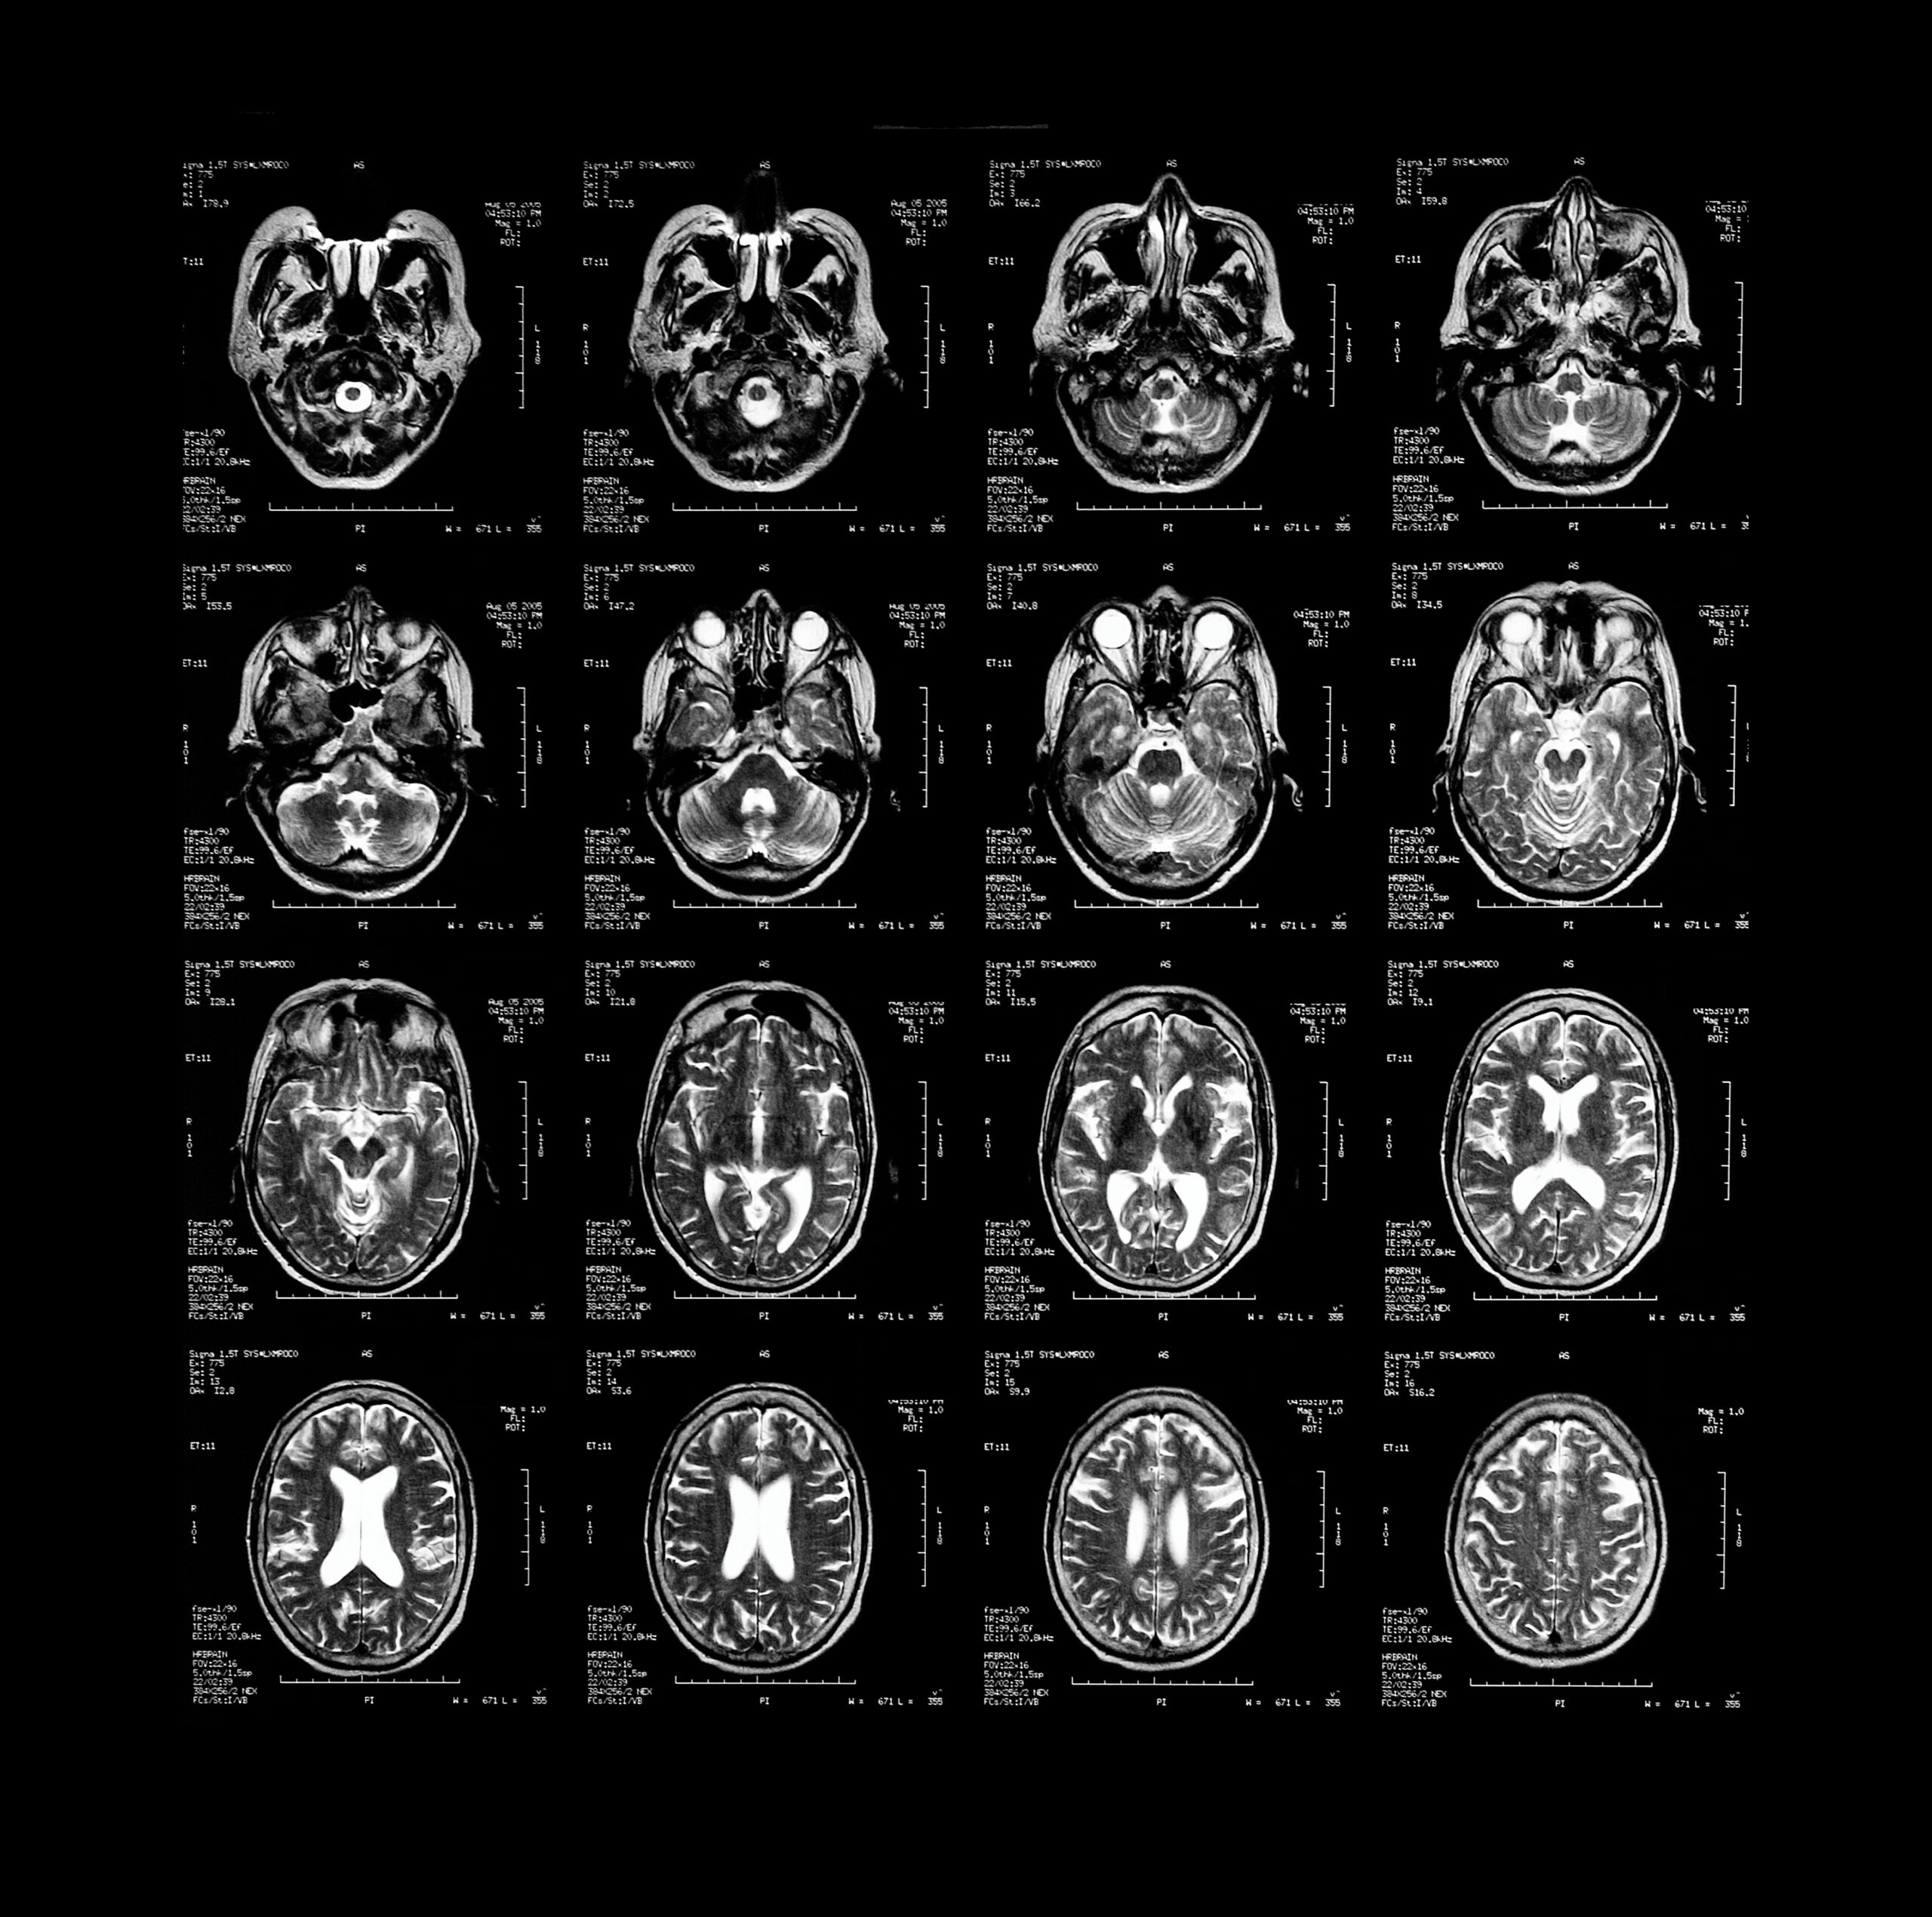

brain scans

Brain scans have shown that psychopaths might have defects in regions related to impulse control and emotional processing. Callista Images/Getty Images